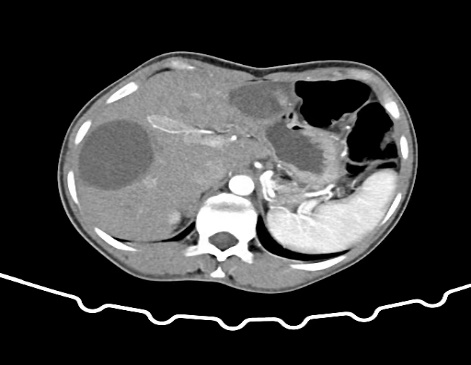

关注近日,阿里地区人民医院迎来了一项重大突破:成功为一名28岁女性患者实施了首例肝包虫病手术。患者体重40Kg,身高140cm,BMI指数为20,因“体检发现肝包虫5年,肝区疼痛1年”入院。经过B超和上腹部增强CT检查,诊断为肝囊型包虫病(CE₃型),肝脏S3段和S6、7段分别发现8×7cm和9×8cm的囊性病灶。

11月19日,手术团队在术中联合控制中心静脉压,采用Pringle法间断阻断肝门,精准定位外囊与肝组织的界限,成功避免了损伤门脉分支及胆管等重要结构,保持囊壁完整性。术中出血仅约100ml,成功完成了“肝左叶S3切除,右叶包虫外囊摘除术”。术后患者恢复良好,病理报告显示外囊完整囊性肿物,内有粉皮样物,符合包虫病特征。